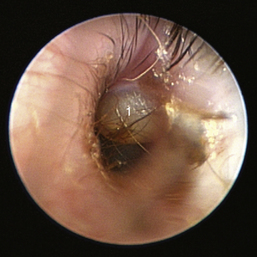

image

Figure 20-18 Nasopharyngeal polyp in the horizontal ear canal of a cat.